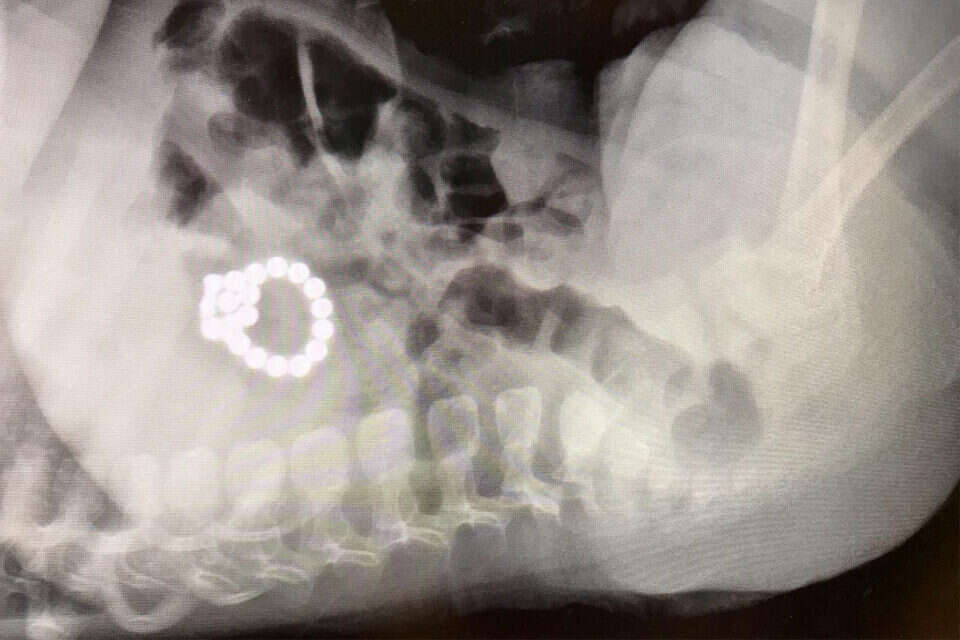

צוות גסטרו ילדים התארגנו במהירות וביצעו שוב אנדוסקופיה כדי לאתר מגנטים נוספים ורק לאחר מאמצים רבים ראו הרופאים שהם תקועים בדופן התריסריון. "יצאנו אל המשפחה המתוחה והסברנו את הצורך בניתוח במהלכו נמצא שהמגנטים יצרו חיבור בין הקיבה לתריסריון ולולאת מעי דק", העידו הרופאים, "לאחר פירוק החיבור, ניתן היה להוציאם ולסגור את החורים". לבסוף, התינוק התאושש מהר מהניתוח והוא ישתחרר מבית החולים בימים הקרובים.

המגנטים לאחר שהוצאו בניתוח, דוברות הדסה